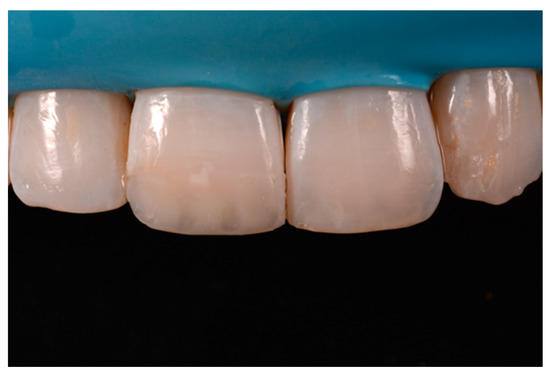

A wise balance of these opaque and translucent shades represents the key factor in obtaining reliable esthetic outcomes and great attention should be paid for their correct positioning [10,27]. Nevertheless, it happens that, during the restorative procedures, some inaccuracies could be made resulting in having opaque shades in place of translucent ones. This is generally realized too late, after finishing and polishing procedures thus compromising the final esthetic result [25]. In Figure 58 in fact the esthetic outcome of the left central incisor could have been improved if the opaque incisal margin had been made thicker and festooned. Conversely, we can notice from Figure 59 excessive thickness in the opaque incisal margin that, if not reduced, could provide an unpleasant final esthetic result.

Figure 59.

Completing the restorations without previously reducing the incisal frame could provide an unpleasant final esthetic outcome.